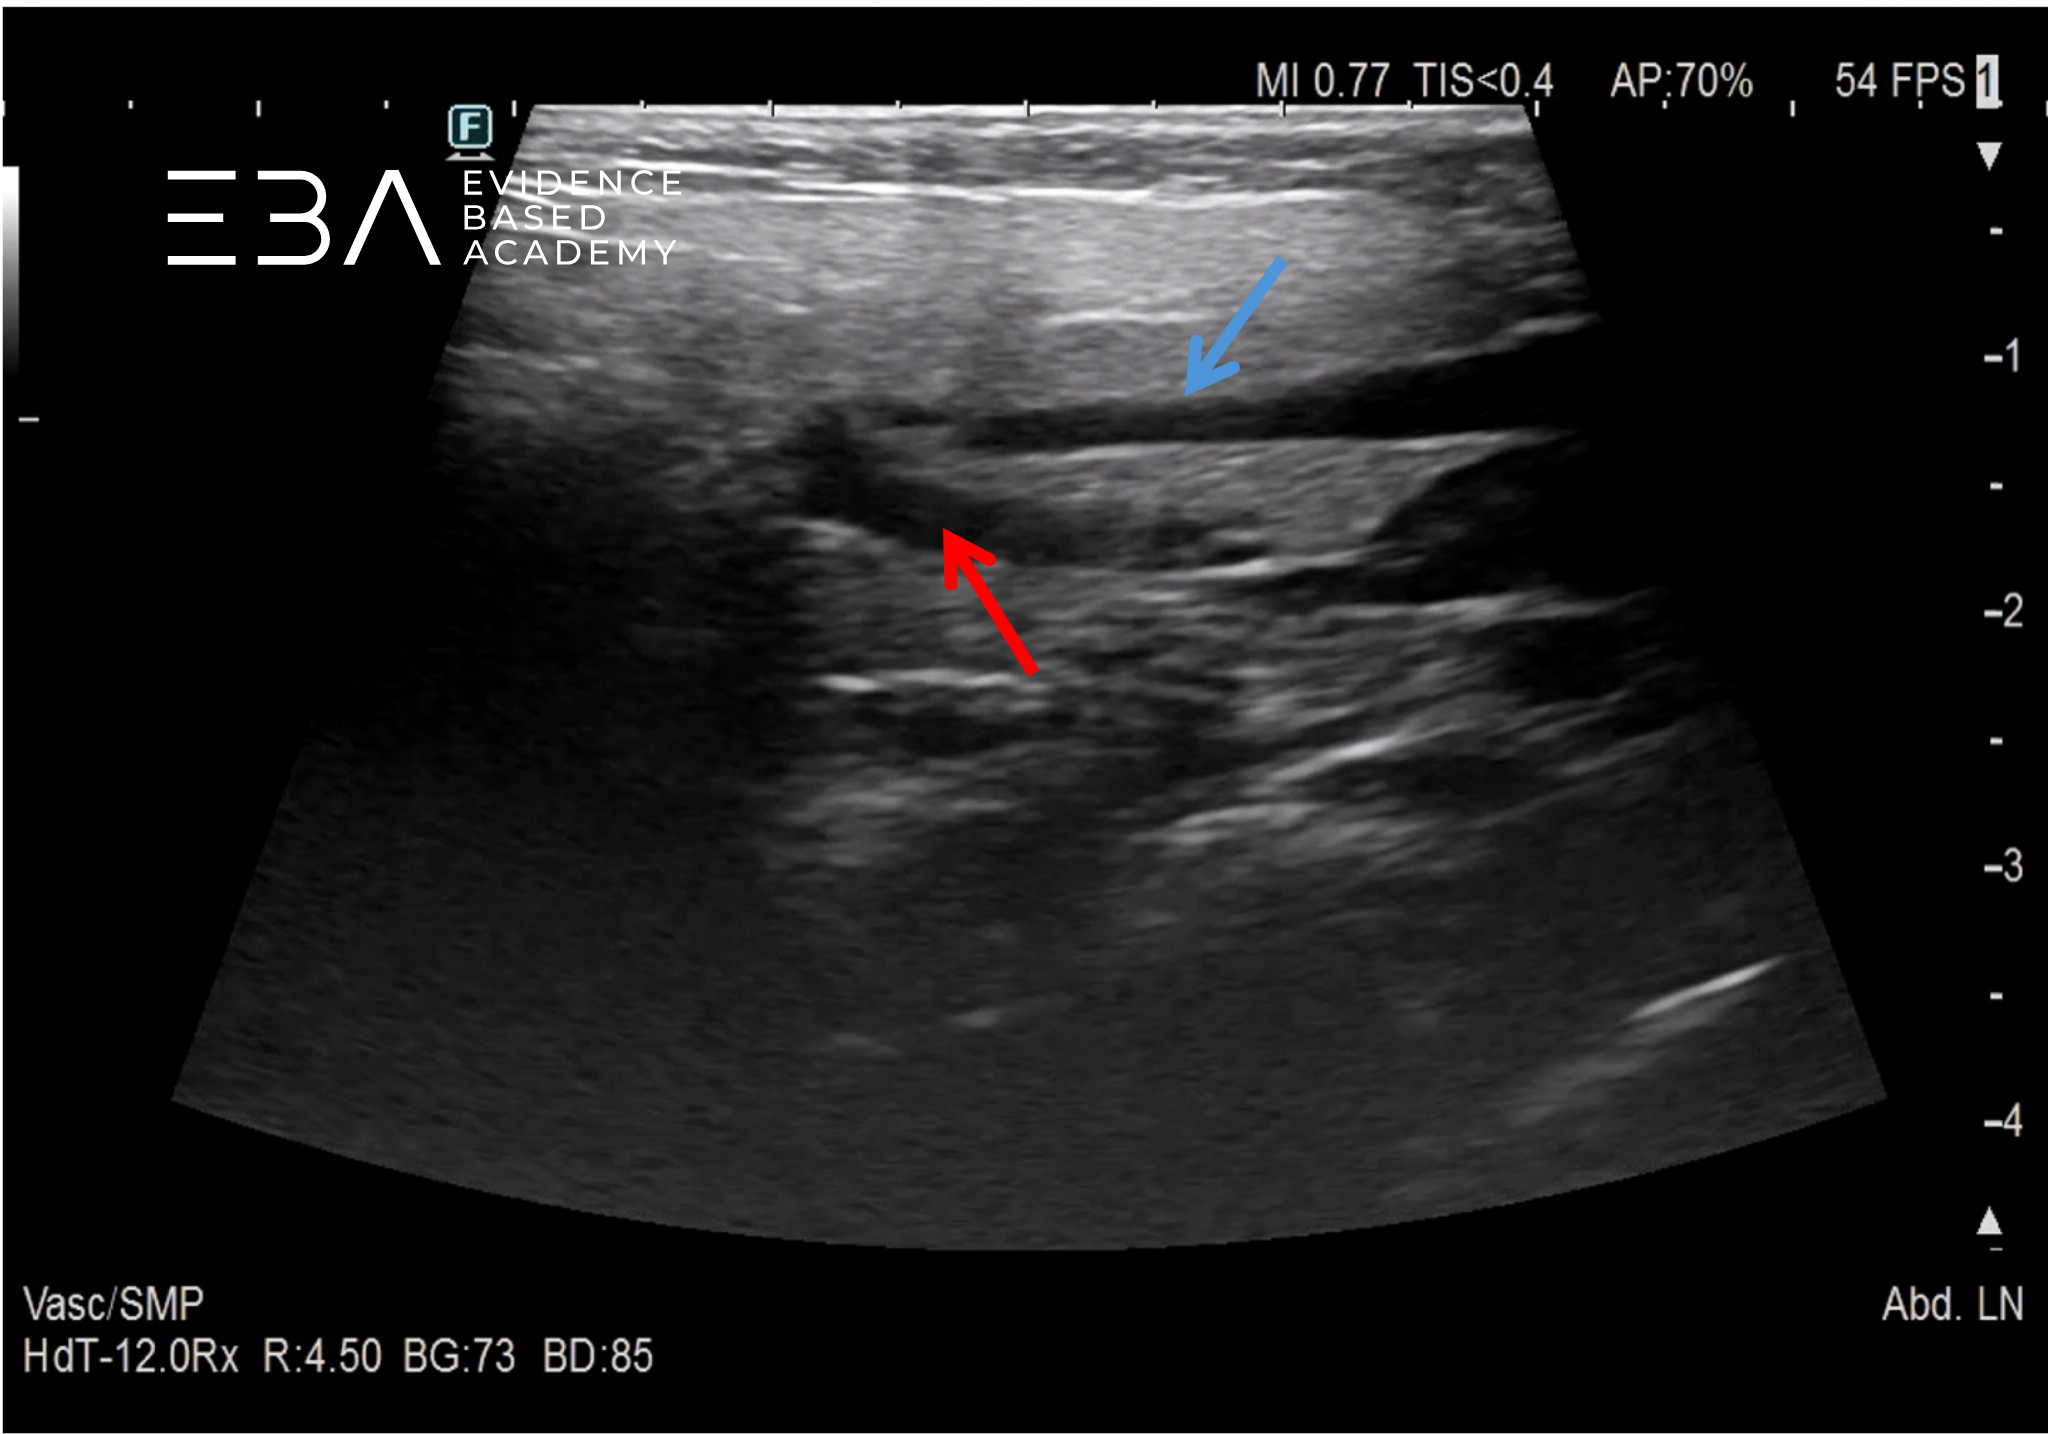

11. Projekcja podżuchwowa – pomarańczową strzałką oznaczono śliniankę podżuchwową, niebieską strzałką śliniankę podjęzykową.